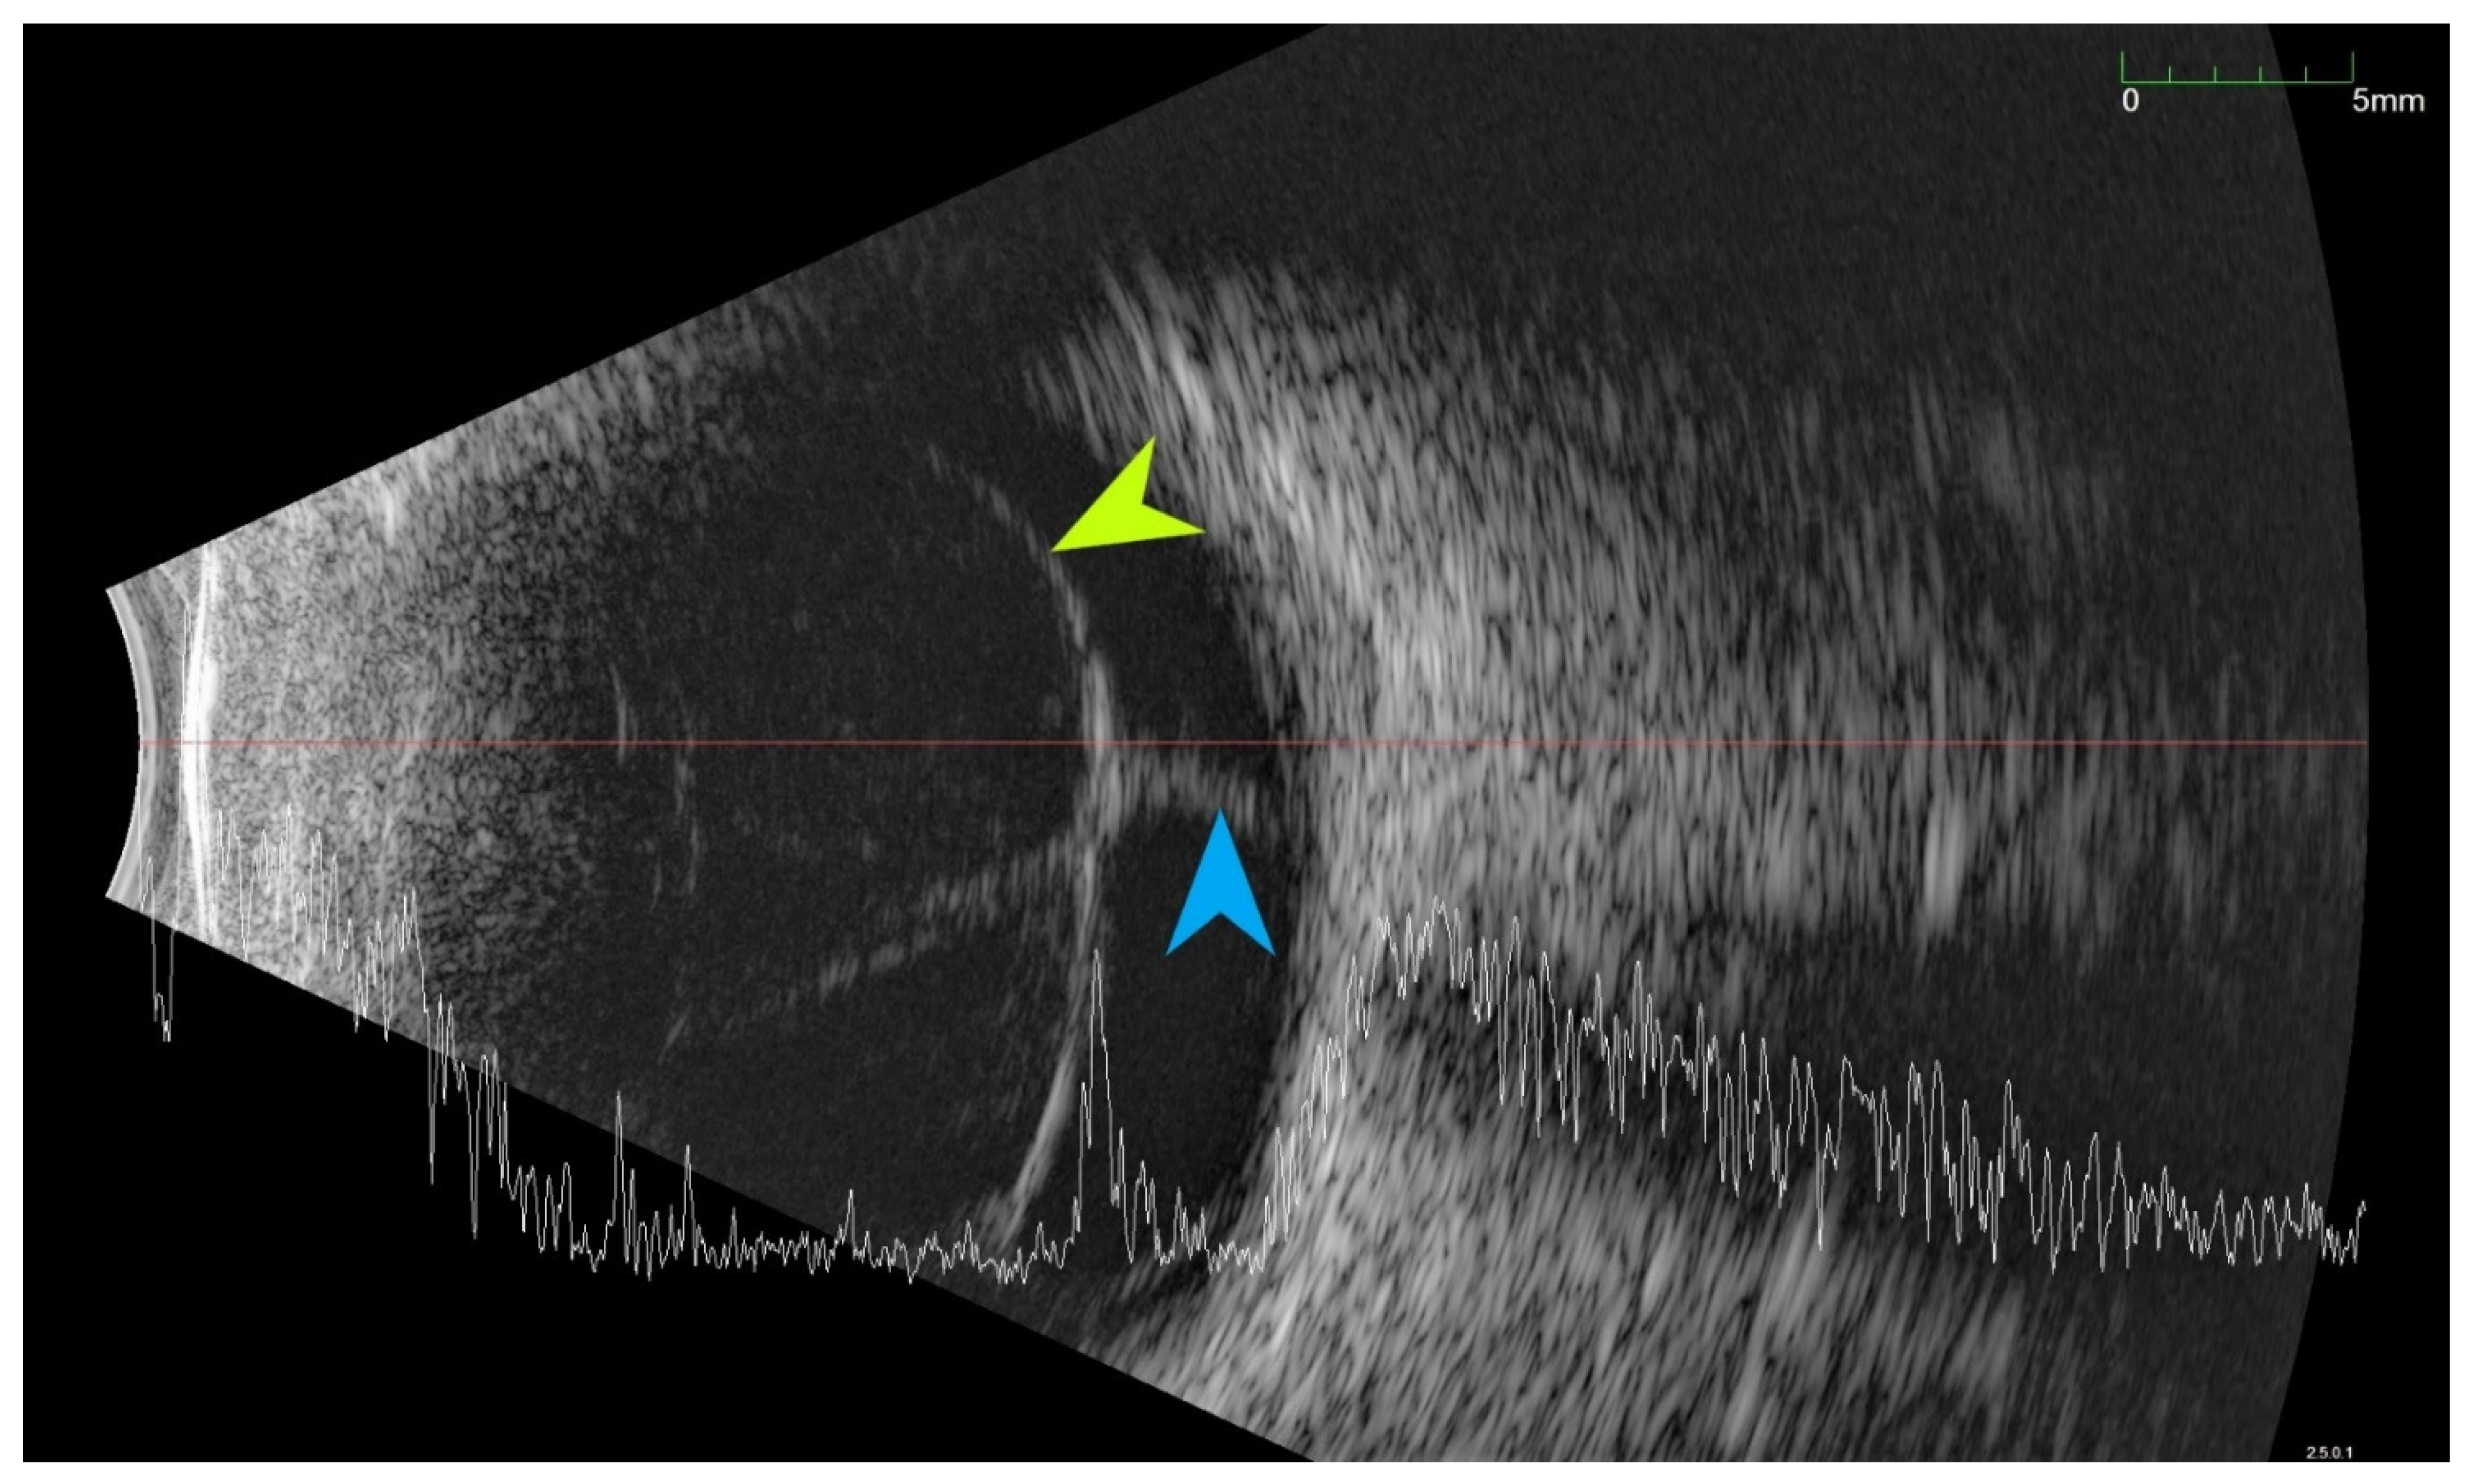

All of the above circumstances make the assessment of the vitreous body and retina in an ophthalmoscopic examination often impossible. The basic diagnostic tool in such cases is an ultrasound examination. Vitritis is inherent part of EE. Ultrasonography is nonspecific, however, it can indicate severity of the posterior involvement (Figure 6 and Figure 7) [80]. It also allows the assessment of the progression of changes (Figure 8). Features characteristic for EE include strands and membranes with reduced mobility (Figure 9). Other common changes are retinal detachment and subretinal abscess (Figure 10).

Ultrasound B scans showing the evolution of changes during the development of inflammation. (A,B)—vitritis, posterior vitreous detachment (blue arrow), and retinal thickening. (C,D)—retinal detachment (green arrow) and numerous hyperechoic densities in the vitreous chamber (blue arrowhead).

Ultrasound examination showed hyperechoic densities and point tractions on the retina (blue arrowhead). Densities forms strands and membranes with reduced mobility (green arrowhead). In order to confirm that the retina is not detached, the A-scan was superimposed over B-scan.